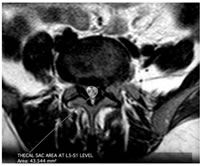

CASE 1

LUMBARIZED S1 VERTEBRA IS NOTED

T1W PARASAGITTAL IMAGE SHOWING MODERATE THECAL SAC STENOSIS ON THE LEFT (OBLITERATION OF FAT PLANE) ABUTTING THE L5 EXITING NERVE ROOT AT L5-S1 LEVEL

T1W AXIAL IMAGE SHOWING SEVERE THECAL SAC STENOSIS (<75 mm2) AT L5-S1 LEVEL DUE TO DIFFUSE DISC BULGE AND LIGAEMETNUM FLAVUM HYPERTROPHY AND FACETAL ARTHROPATHY